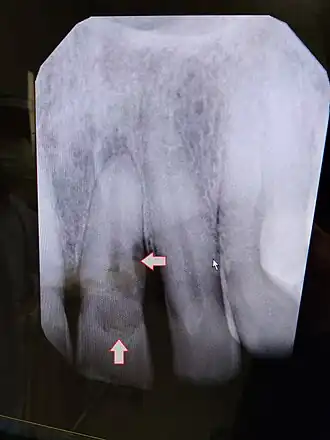

![]() | |

| Post traumatic External tooth resorption 9 | |